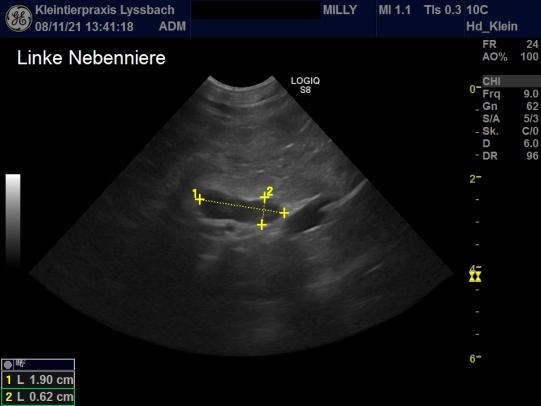

Die Vorgeschichte (Gangprobleme, erhöhte Trinkmenge, eingeschränkte Sehkraft) und die Untersuchungsergebnisse (Hautveränderungen und Hautqualität, neurologische Defizite, erhöhter Blutzucker) wecken den Verdacht, dass Milly an einer bei Katzen seltenen Nebennierenüberfunktion leiden könnte. Zum Beweis der Erkrankung müssen weitere Bluttests (Dexamethason-Hemmtest) und eine CT- oder MRT-Aufnahme durchgeführt werden; allerdings kann auch eine Ultraschalluntersuchung wertvolle Hinweise liefern. Tatsächlich ist im Ultraschall ersichtlich, dass beide Nebennieren von Milly stark vergrössert sind: Normalerweise ist dieses Organ bei der Katze etwa 11 Millimeter lang und 4.3 mm dick; bei Milly sind die Nebennieren mit ca. 19 mm x 6 mm viel grösser. Mit sehr hoher Wahrscheinlichkeit leidet die Katze an einer Nebennierenüberfunktion (Hyperadrenocorticismus) und parallel verlaufender Zuckerkrankheit (Diabetes Mellitus).